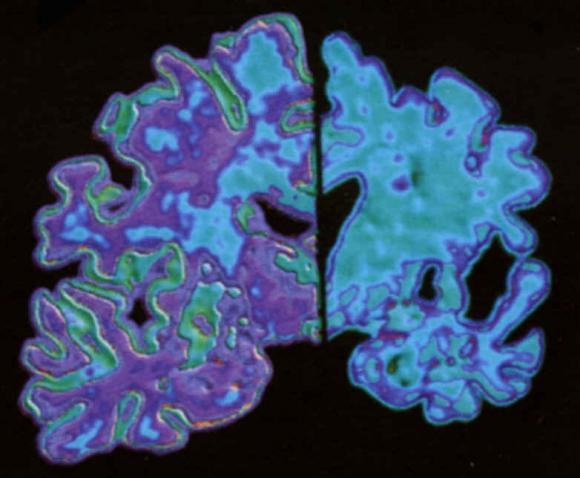

Ambos expertos señalan la importancia de realizar pruebas que puedan detectar la enfermedad en fase temprana. Una de las opciones que se barajan es el desarrollo de bioquímicos, por ejemplo de la proteína del amiloide, o una resonancia magnética que permita conocer si, el patrón de atrofia del cerebro es típico de Alzheimer. De este modo, podría realizarse un diagnóstico aún cuando la persona está realizando una vida normal, siendo éste el momento perfecto para empezar el tratamiento.

¨Actualmente el diagnóstico con síntomas pero sin demencia es posible, pero el diagnóstico sin síntomas continúa en fase de investigación¨, explica Martínez-Lage. ¨Si cuidamos los factores de riesgo vascular a lo largo de la vida, especialmente de los 45 años en adelante, estaremos haciendo que nuestro cerebro llegue a las edades de 65-70 años en un estado más saludable y por tanto más dispuesto para soportar una enfermedad de Alzheimer existente¨, añade.